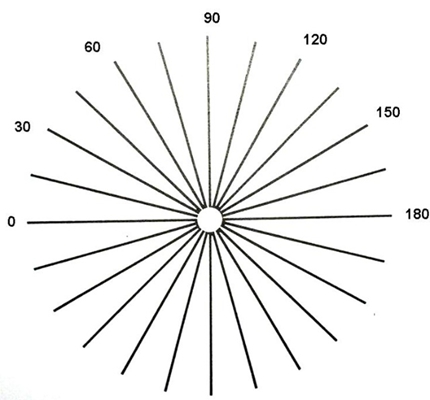

A:判斷自己有沒有散光,最簡單的方法是使用散光表來測試。散光表是一種簡單、方便的方法,但是它的準確度不是特別精確。在配鏡的情況下一般再用裂隙法,或者是交叉圓柱鏡法來精調散光的度數。散光表在網上可以看到,它類似於鐘錶的盤面,有12個數字。各個鏡線……